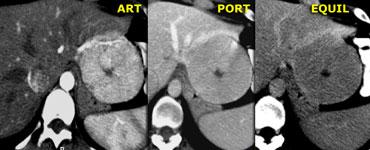

Bên trái là hai tổn thương tăng sinh mạch kề nhau với ngấm thuốc đồng nhất trong pha động mạch và sẹo trung tâm giảm tỷ trọng trong pha động mạch và tĩnh mạch, ngấm thuốc trong pha cân bằng.

Đây là đặc điểm điển hình của FNH.

Lưu ý rằng tổn thương FNH nhỏ hơn, nằm phía trước và bên phải tổn thương lớn hơn, có cùng kiểu ngấm thuốc.

Trong pha động mạch muộn, FNH điển hình biểu hiện ngấm thuốc đồng nhất sáng, nhưng kém đậm hơn động mạch chủ, với sẹo trung tâm giảm tỷ trọng.

Các dải xơ hoặc vách ngăn giảm tỷ trọng tỏa ra từ sẹo không phải là hiếm gặp và khá đặc trưng.

Trong pha cửa, FNH thường đồng tỷ trọng với nhu mô gan bình thường và có thể khó xác định ranh giới.

Pha muộn thường cho thấy tăng tỷ trọng của sẹo trung tâm và các vách ngăn do ngấm thuốc muộn của các thành phần xơ.

Không nên thấy vôi hóa, tính không đồng nhất hoặc vỏ bao trong FNH.